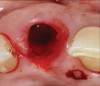

Prior to the initiation of the surgery, the surgical guide was tried in to confirm proper seating and stability (Figure 15). A flapless approach was not considered because the need for further bone grafting at the time of implant placement had been anticipated through the digital planning. A slightly palatal crestal incision was made, followed by two vertical incisions on the mesial and distal aspects of the edentulous site in order to preserve the papilla and avoid additional esthetic compromise to the anterior sextant. Next, a full-thickness flap was elevated to facilitate removal of the tenting screw and permit visualization of the buccal plate (Figure 16). A standard guided protocol was followed to place the implant, and its final position mirrored that of the digital plan. As predicted, the prosthetically driven implant position resulted in an insufficient buccal plate (Figure 17); therefore, additional guided bone regeneration was performed to reinforce the area and prevent future breakdown (Figure 18 and Figure 19). Making periosteal incisions could have compromised the blood supply to the flap, so instead, it was stretched in order to achieve tension free coronal advancement.31The flap was secured utilizing horizontal mattress sutures with additional supportive interrupted sutures to ensure primary closure (Figure 20). An immediate postoperative periapical radiograph (Figure 21) and CBCT scan (Figure 22) were taken, demonstrating a final implant position centered with the planned location of the gingival zenith.

(17.) Implant placed 1-mm distal to the midline of the edentulous space, corresponding with the planned location of the gingival zenith. Note the lack of sufficient bone buccal to the implant that necessitated further grafting.

Figure 17